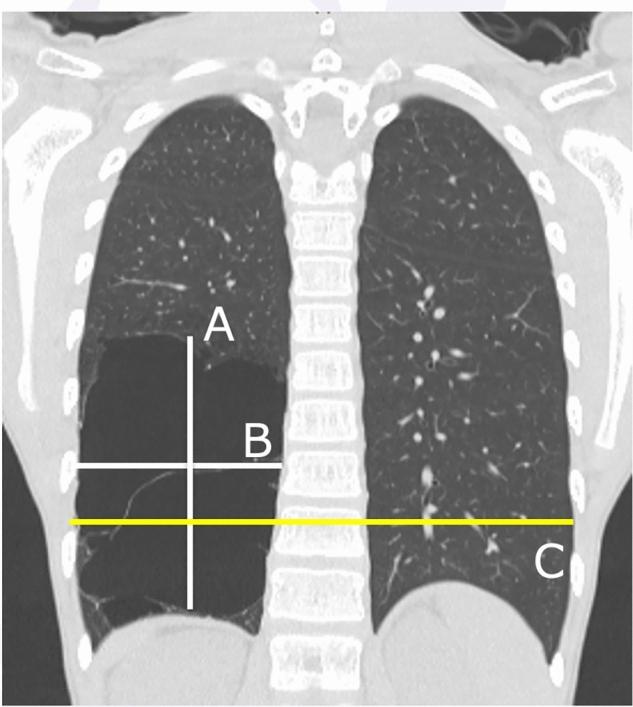

囊性肺疾病术后漏斗胸和脊柱侧弯危险因素的评估

This study examined patients who underwent surgery for cystic lung disease (open and thoracoscopic) between July 2000 and December 2018 with a > 3-year follow-up period. Lesion size, surgical outcomes, and subsequent musculoskeletal complications were compared between the open surgery and thoracoscopic surgery groups. Univariate and multivariate analyses were performed to identify predictive factors.

RESULTS

Overall, 90 patients (19 and 71 patients in the open and thoracoscopic groups, respectively) were included in this study. There was no significant difference in the incidence of pectus excavatum or scoliosis between open and thoracoscopic surgery; however, Haller's index and Cobb angle were significantly higher in the open surgery group. In the univariate analysis, neonatal surgery and lesion size were substantial predictors of musculoskeletal malformations.

CONCLUSION

Postoperative musculoskeletal deformities emerge after surgical treatment for cystic lung disease, with thoracoscopic surgery showing advantages in selected dimensions. Neonatal surgery and lesion size are pivotal prognostic factors for musculoskeletal complications. Further corroborative multicenter studies are imperative to substantiate these findings and foster enhanced patient outcomes.